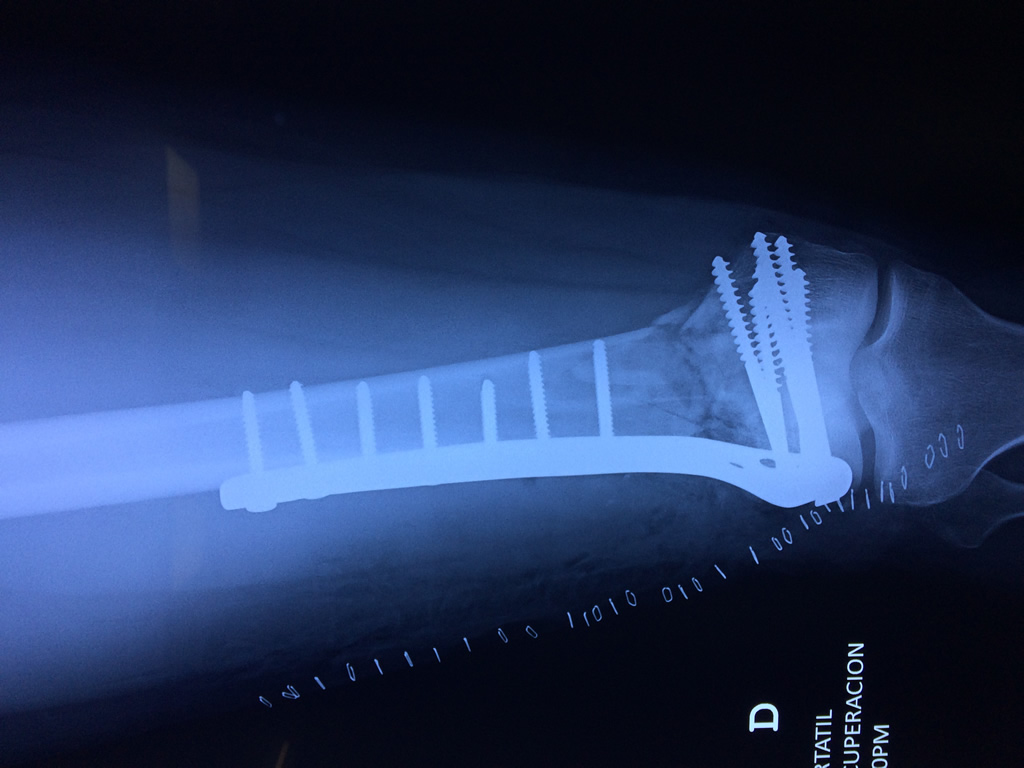

El fémur es el hueso del muslo, el segundo segmento del miembro inferior. Es el hueso más largo, fuerte y voluminoso del cuerpo humano.